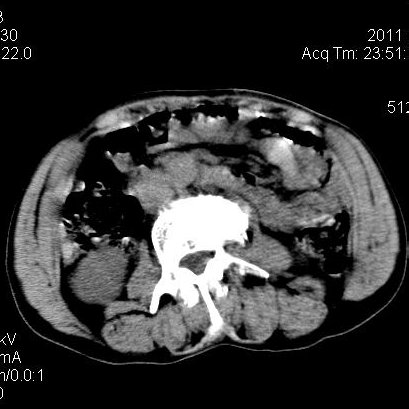

肝左叶发育异常

男性,55岁,骑摩托车摔倒后入院,自述右上腹疼痛

[backcolor=#FF0000]第一次诊断的时候也是这么肯定,可是床旁超声检查并没有发现明显异常,而且患者的一般症状都良好。还好临床只是保守治疗,没有立即手术,第二次复查的时候没有一点变化,又做了MRI检查,没有血肿,

这是一例肝左叶发育异常的,很个性吧~[/backcolor]